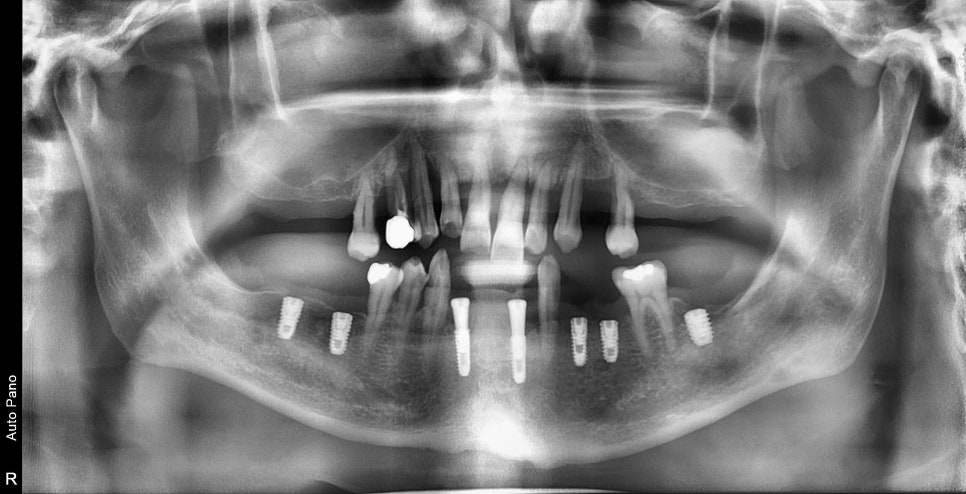

순차적인 임플란트 수술 시작

비염 제거 수술을 하고 점막이 안정화되는 기간 동안

아래쪽 임플란트를 먼저 수술하고 필요한 치료를

먼저 진행하기로 했습니다.

뼈와 임플란트와 고정이 약해서 수술 기간 동안

임시틀니를 껴야 하지만 기간을 최소화하기 위해

아래쪽 먼저 임플란트를 완성하기로 하고 그에 따른

위쪽은 수술 후 교합을 완성하기로 했습니다.

비교적 동요도가 없고 뿌리가 튼튼한 치아는 최대한

살려서 지내는 방향으로 계획을 잡았습니다.

이비인후과 수술 후 경과

이비인후과에서 비염 수술을 하신 후

3달 정도가 지난 사진입니다.

과거에 상악동을 채우고 있던 희뿌옇던 염증이 사라졌지만

만성 염증에 의해 점막이 부어있습니다만

이 정도는 상악동거상술을 하기에는 방해요소는 아닙니다.

상기 환자는 남아있는 잔존골의 양이 너무 적기 때문에

측면에서 접근하는 측방접근법을 이용하여

치조골 이식술과 동시에 임플란트 수술을 했습니다.